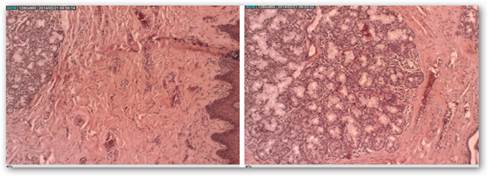

The histopathologic study of the surgical specimen obtained confirmed the clinical diagnosis. The two histological sections of the case presented here (Fig. 4) show, respectively:

- A panoramic view of labial mucosa.

- The submucosa of the lip with an abundance of collagen fibers, as well as a large number of mucous lip salivary glands.

Histological examination showed masses of loose connective tissue, associated with numerous mucous salivary glands, like the ones normally occurring in the area1,12, which is consistent with the histopathologic study of the surgical specimen obtained.